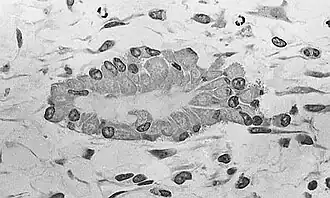

![]() Osteoblasts (purple) rimming a bony spicule (pink - on diagonal of image). In this routinely fixed and decalcified (bone mineral removed) tissue, the osteoblasts have retracted and are separated from each other and from their underlying matrix. In living bone, the cells are linked by tight junctions and gap junctions, and integrated with underlying osteocytes and matrix H&E stain. | |

Morphology and histological staining

Hematoxylin and eosin staining (H&E) shows that the cytoplasm of active osteoblasts is slightly basophilic due to the substantial presence of rough endoplasmic reticulum. The active osteoblast produces substantial collagen type I. About 10% of the bone matrix is collagen with the balance mineral.[29] The osteoblast's nucleus is spherical and large. An active osteoblast is characterized morphologically by a prominent Golgi apparatus that appears histologically as a clear zone adjacent to the nucleus. The products of the cell are mostly for transport into the osteoid, the non-mineralized matrix. Active osteoblasts can be labeled by antibodies to Type-I collagen, or using naphthol phosphate and the diazonium dye fast blue to demonstrate alkaline phosphatase enzyme activity directly.

Light micrograph of decalcified cancellous bone displaying osteoblasts actively synthesizing osteoid, containing two osteocytes -

Light micrograph of undecalcified tissue displaying osteoblasts actively synthesizing osteoid (center) -

Light micrograph of undecalcified tissue displaying osteoblasts actively synthesizing rudimentary bone tissue (center) -

Osteoblasts lining bone (H&E stain)